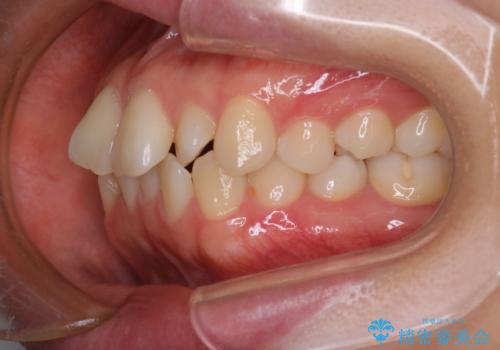

- 「前歯が出ているのが気になる」との主訴で来院されました。診察の結果、上下の前歯が前方に突出し、口元がやや目立つ印象でした。また、歯列の中心線(正中)も上下でずれており、かみ合わせのバランスにも問題がありました。

抜歯をせずに口元の突出感を改善するためには、奥歯を後方に動かして前歯を引くスペースをつくる必要があります。そこで、インビザラインによるマウスピース矯正に加え、TAD(矯正用アンカースクリュー)を併用する治療計画を立てました。TADを固定源とすることで、効率的に奥歯を後方へ動かし、非抜歯でも前歯をしっかり引き下げることが可能になります。